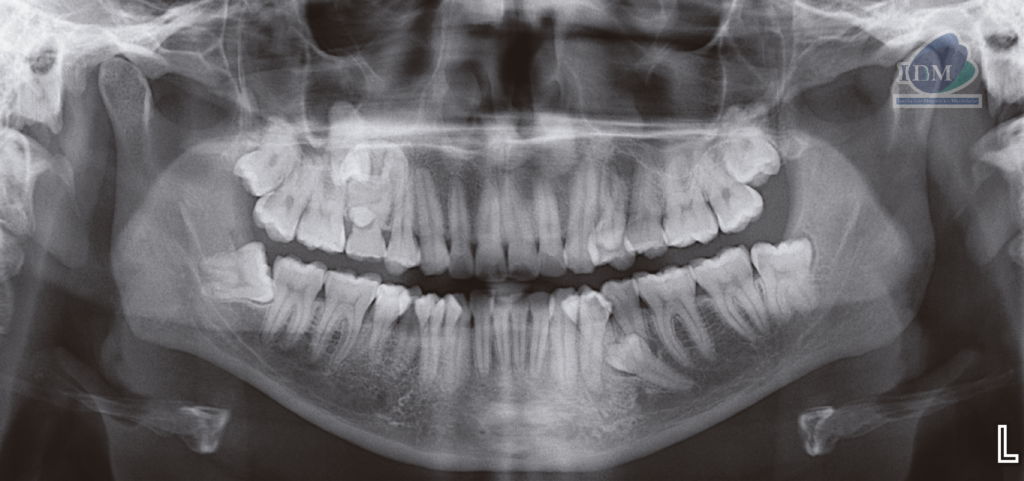

En la radiografía panorámica (Figura 1), se aprecia pieza supernumeraria proyectada entre pieza 55 y pieza supernumeraria 2, imagen radiopaca de densidad dentaria proyectada sobre zona de pieza 15, de limites definidos y forma irregular.

Radiografia Panorámica